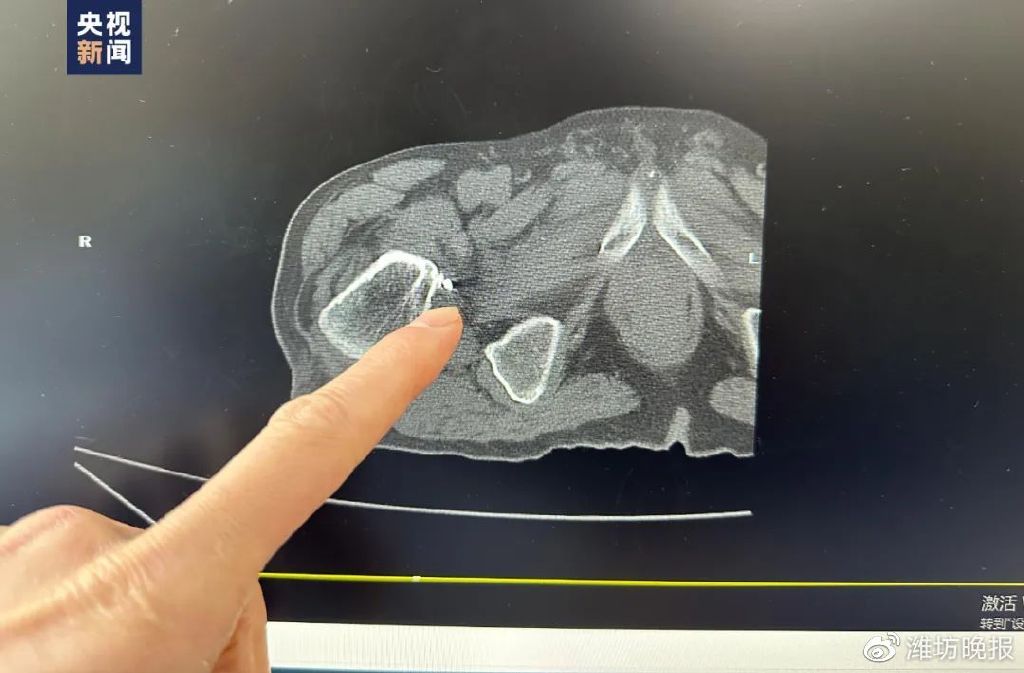

检查时意外发现髋关节处

有战争时期残留的多块弹片

医生发现

他的髋关节里竟然残留着多块弹片

医生表示

这些弹片位于髋关节的内侧缘

距体表有十几厘米深